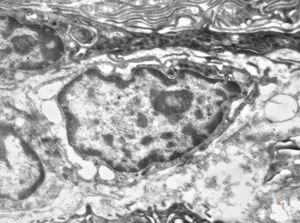

F,41y. | synovial metaplasia - capsule of implantate